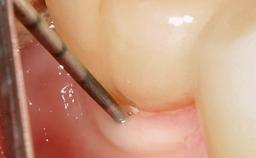

Paolo Casentini demonstrates that peri-implantitis can be successfully treated even at an advanced stage. He discusses a case in which the existing implants and prostheses were both retained while regenerating the defect and creating a band of keratinized tissue. A 69-year-old female patient was referred by her general dentist for evaluation of a recurrent infection at previously placed and restored implants in the posterior left mandible. The patient’s chief complaint was recurrent swelling and pain in the molar region of the left posterior mandible with discomfort during brushing in the same area. The patient reported receiving two implants (36 and 37) nine years earlier.